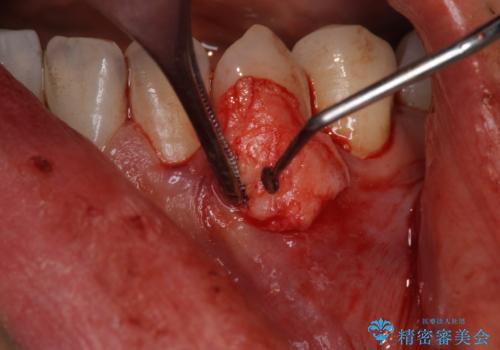

- 下の犬歯の歯茎の下がりを気にされていました。

矯正治療予定であったので、矯正治療前に歯茎の移植を行い、さらに退縮するのを防ぎました。

下がったのを元に戻すことは必ずしもできないですが、厚みを増やして下がりにくくすることはできます。今回左下の犬歯は特に、しっかり下がったのも元に戻すことができ、大変うまくいきました。